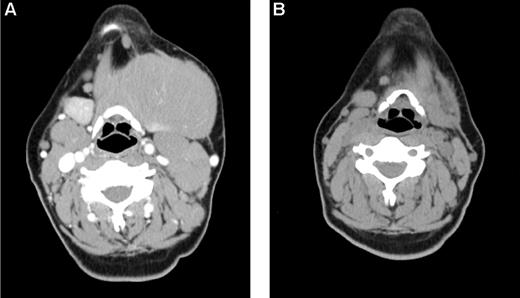

Early objective responses at 1 and 3 months were observed in 19 (48%, 3 CR/complete remission unconfirmed [CRu], 16 PR) and 24 (60%, 14 CR/CRu, 10 PR) patients, respectively, including 17 (59%) objective responses in the 29 patients with known chemoresistant disease and 10 (59%) of 17 with bulk more than 5 cm. Three-month responses were seen in 5 (38%, 5 CR) DLBCL, 9 (90%, 4 CR, 5 PR) CLL/SLL, 4 (50%, 2 CR, 2 PR) MCL, and 5 (83%, 3 CR, 2 PR) FL patients. The MZL and HCL patient achieved a PR and stable disease, respectively, by month 3. There was no significant difference in response between patients with DLBCL transformed from FL (3 CR) and those with de novo DLBCL (2 CR). In total, 33 (83%) patients experienced reduction in the measurable disease burden by day 84. Early response by histology and chemosensitivity is quantified in Figure 2. Figure 3 illustrates an example of an early response observed in a patient with highly chemoresistant, bulky CLL/SLL.

Early response in bulky, chemoresistant lymphoma. A 33-year-old woman with CLL/SLL had a partial response lasting 10 months after initial therapy with 6 cycles of fludarabine-R and then experienced progressive disease while receiving pentostatin-cyclophosphamide-R, and continued progressive disease while receiving CHOP. (A) Baseline image reveals a dominant 12 cm left submandibular mass. She was treated with 32 mCi of 90Y-ibritumomab tiuxetan, fludarabine, 2 Gy TBI, and a matched unrelated allogeneic transplant and achieved a PR by after transplantation day 28 (B) and complete remission by day 84. The patient remains alive and disease-free 3 years after transplantation.